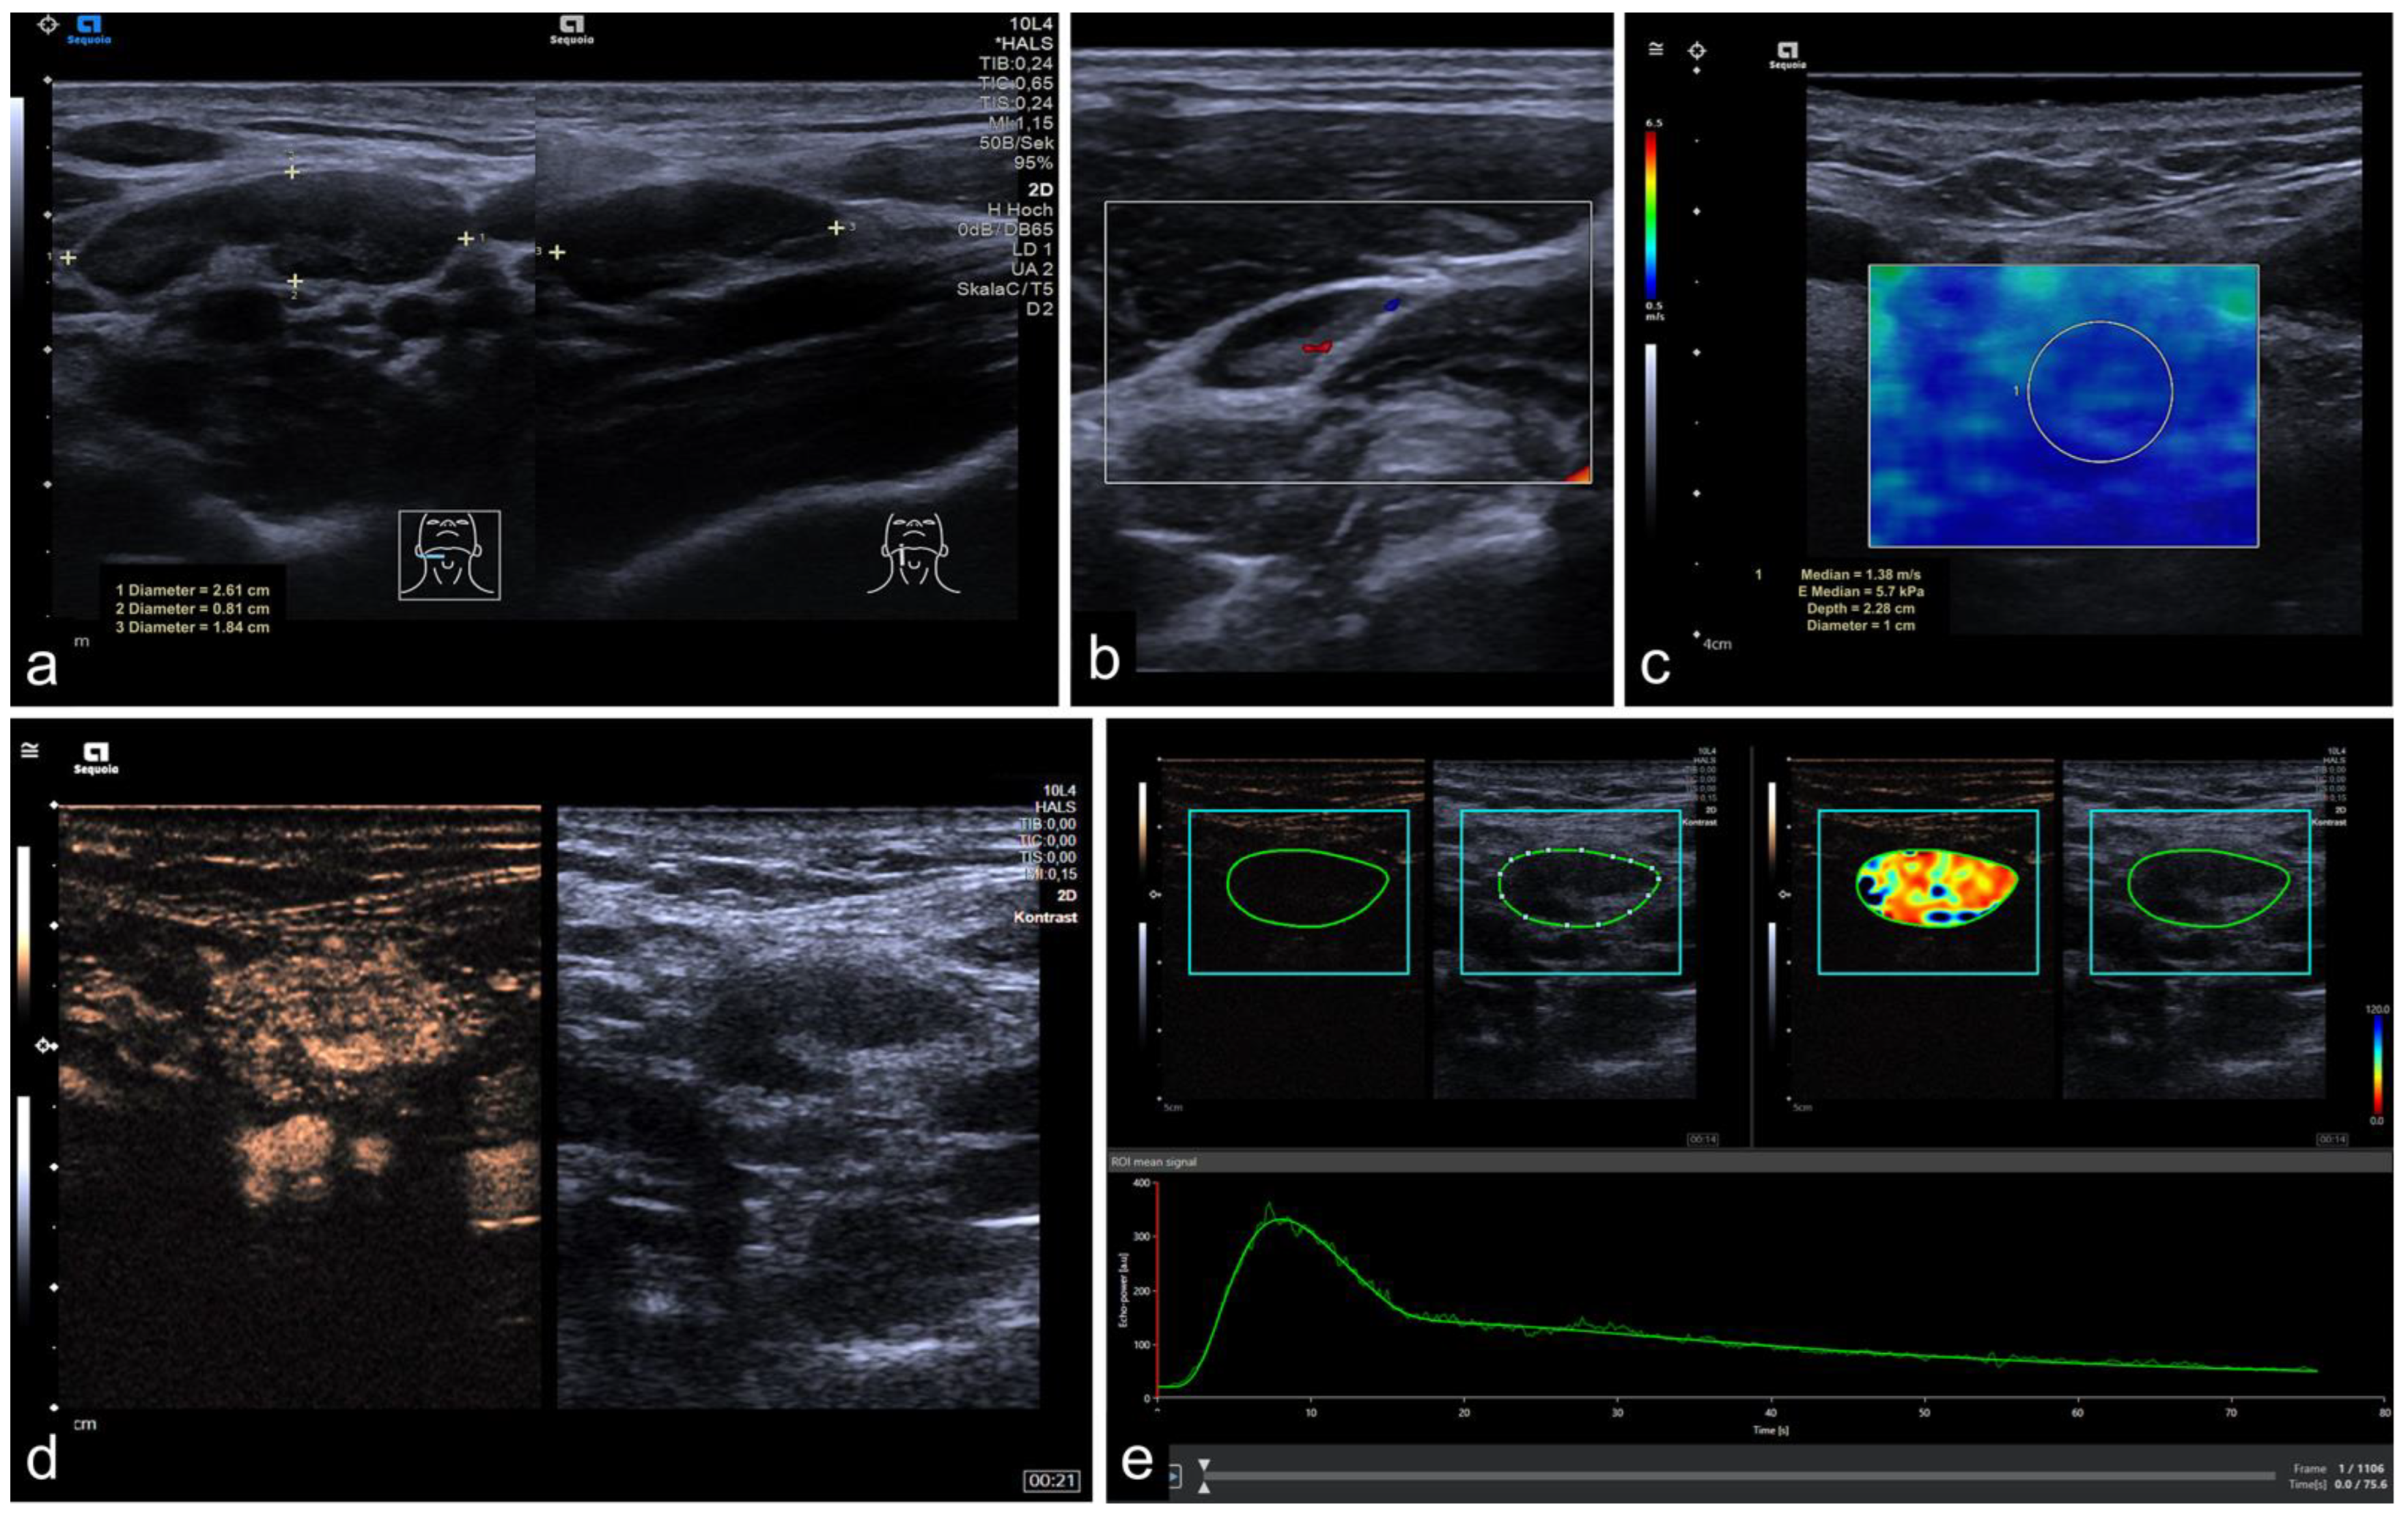

2.2. Imaging Protocol

2.3. Perfusion Analysis